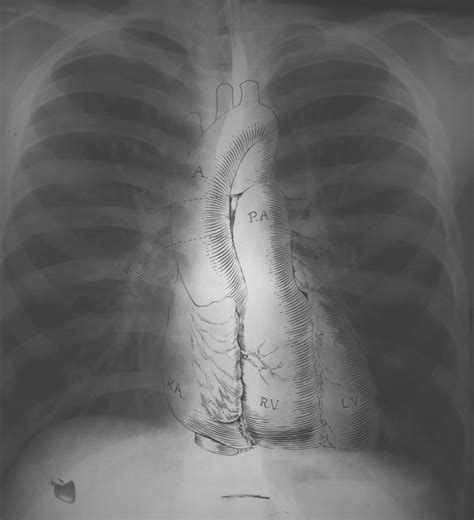

First things first, let’s break down what a chest X-ray actually is . A chest X-ray, also known as a radiograph, is a non-invasive medical test that uses electromagnetic radiation to create images of your chest. These images allow doctors to visualize the structures inside your chest, including your lungs, heart, blood vessels, airways, and bones. Doctors often use chest X-rays to diagnose a wide range of conditions, from pneumonia and heart failure to broken ribs and lung cancer. It’s a quick and relatively painless procedure, making it a valuable tool in medical diagnostics. The images produced are in grayscale, with dense structures like bones appearing white, air appearing black, and soft tissues appearing in varying shades of gray. This contrast helps doctors differentiate between different structures and identify any abnormalities.

Okay, so what exactly are doctors looking for when they say an X-ray is “normal”? Basically, a normal chest X-ray shows clear lungs, a heart of normal size and shape, and healthy-looking blood vessels. The bones, like your ribs and spine, should also appear intact and without any signs of fractures or abnormalities. Think of it like a well-organized room – everything is in its place, and there’s nothing out of the ordinary catching your eye.

In a normal chest X-ray, the lungs should appear clear and dark. The darkness indicates that the lungs are filled with air, which is a good sign. The blood vessels within the lungs will be visible as faint, branching lines. There should be no signs of consolidation (areas of increased density), which could indicate pneumonia or other lung infections. The diaphragm , the muscle that separates the chest from the abdomen, should be clearly visible as a smooth, curved line. Any blurring, shadows, or unusual patterns in the lungs would be considered abnormal and warrant further investigation. The absence of these findings suggests that the lungs are healthy and functioning properly. When doctors examine the lungs on an X-ray, they pay close attention to the overall clarity, the presence of any unusual masses or nodules, and the condition of the airways. They also look for signs of fluid accumulation, which could indicate conditions like pulmonary edema or pleural effusion. By carefully assessing these features, doctors can determine whether the lungs appear normal or whether there are any underlying issues that need to be addressed.

The heart should appear in the center of the chest, slightly to the left. Its size and shape should be within normal limits. An enlarged heart, or cardiomegaly, can be a sign of heart failure or other cardiovascular problems. The heart’s borders should be well-defined, and there should be no unusual bulges or indentations. Doctors also assess the position and size of the great vessels , such as the aorta and pulmonary artery. Any abnormalities in these structures could indicate congenital heart defects or other vascular conditions. In addition to the heart itself, doctors also look at the surrounding structures, such as the pericardium (the sac that surrounds the heart). Inflammation of the pericardium, known as pericarditis, can cause fluid to accumulate around the heart, which may be visible on a chest X-ray. By carefully examining the heart and its surrounding structures, doctors can gain valuable insights into the patient’s cardiovascular health.